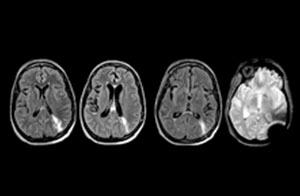

Für Dr. Karis bestehen die nächsten Ziele für die neurologische Notaufnahme in der Umstellung der Untersuchungen für akute Schlaganfall- und TIA-Patienten von CT auf MRT, was eine alternative Managementoption für diese Patienten darstellt. Außerdem wird derzeit die Kooperation mit anderen Abteilungen in die Wege geleitet, was den Nutzen zielgerichteter Untersuchungen mit dem MRT-System in der Notaufnahme noch erhöht. Diese Verbesserungen im Arbeitsablauf können in Kombination mit kürzeren Durchlaufzeiten die Untersuchungsdauer weiter reduzieren.